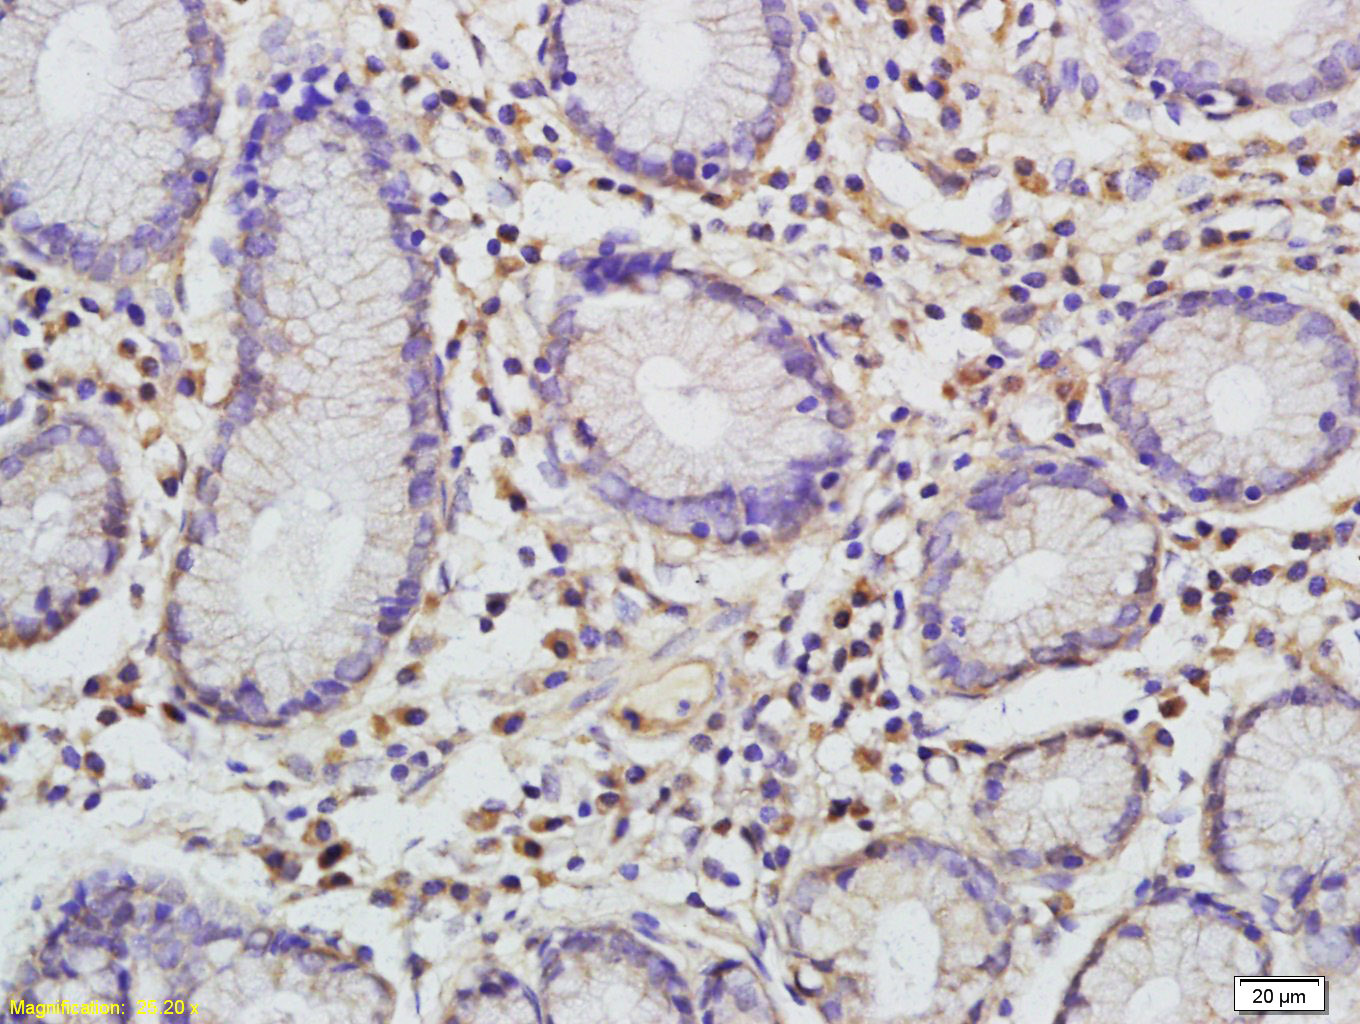

Antigen retrieval: citrate buffer ( 0.01M, pH 6.0 ), Boiling bathing for 15min; Block endogenous peroxidase by 3% Hydrogen peroxide for 30min; Blocking buffer (normal goat serum,C-0005) at 37℃ for 20 min;

Incubation: Anti-I-309/CCL1 Polyclonal Antibody, Unconjugated(bs-10709R) 1:200, overnight at 4°C, followed by conjugation to the secondary antibody(SP-0023) and DAB(C-0010) staining